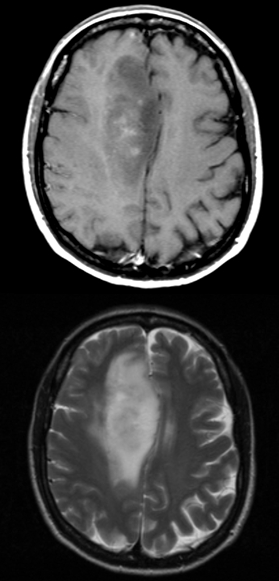

Radiology of pilocytic astrocytomas typically show a mural nodule and a cystic lesion are seen on imaging.